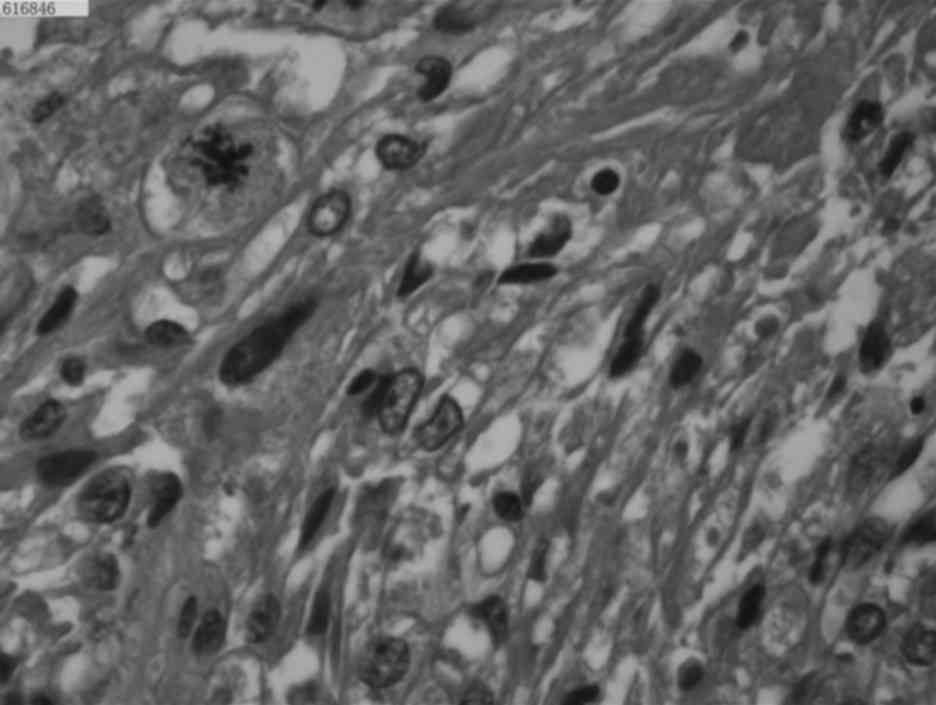

Tuberous sclerosis-associated renal angiomyolipoma: A report of two cases and review of the literature

In the general population, tuberous sclerosis‑associated renal angiomyolipoma (RAML) is a rare benign hamartoma with potentially life‑threatening complications and a poor prognosis. The two patients reported in the present study, who were diagnosed with bilateral RAML and spontaneous rupture of the RAML with tuberous sclerosis, presented with flank pain, abdominal pain, hemorrhage, hematuria and multiple lesions. The two cases are representative examples of the disease, and highlight the importance of determining the risk of acute hemorrhage in the early stages, and the significance of timely and proper treatment.

Figure 1

Figure 2

Figure 3

Figure 4

Figure 5